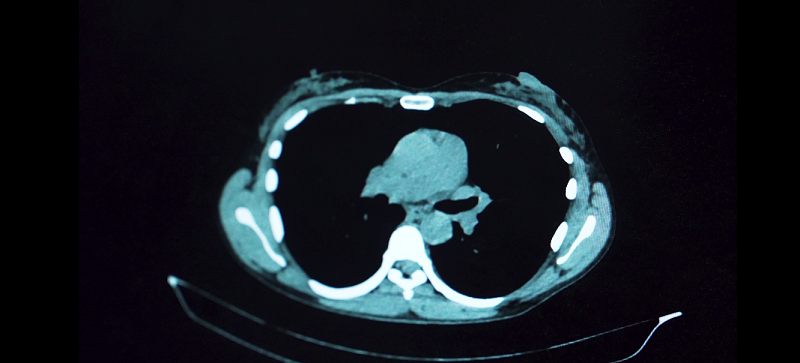

Одним из самых распространённых и опасных онкологических заболеваний считается рак лёгкого: в Мурманской области злокачественное новообразование в органах дыхания диагностируют примерно у 300 человек ежегодно. Из-за того, что опухоль в 72% случаев обнаруживают на III и IV стадиях, наблюдается высокая летальность: около 47% пациентов умирают в течение года после постановки диагноза. При этом около 48% из тех, кто состоит на учёте онкологической службы региона, живут более 5 лет. Всего в Мурманской области на учёте с раком лёгкого в 2023 году находились 852 человека.[1]

Рак легкого характеризуется довольно скудной симптоматикой, скрытым агрессивным течением и стремительным появлением метастазов. Чтобы обнаружить рак легкого на ранних стадиях, необходимо своевременное обращение к врачам при появлении любых подозрительных симптомов.